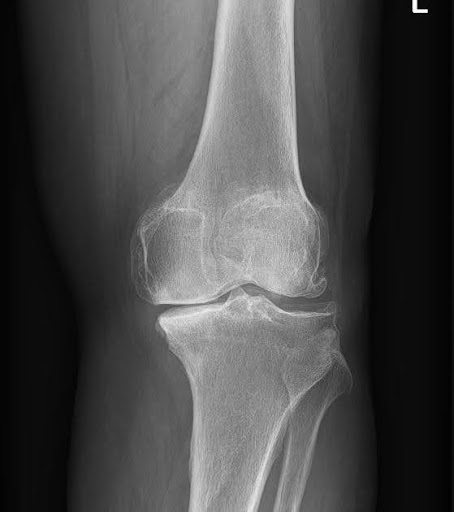

Weight bearing AP view X ray knee showing Grade 3 Knee Osteoarthritis. Regenerative injection treatments are attempted only till Grade 3 Stage of the disease.

Knee osteoarthritis (OA) is a progressive condition where cartilage slowly breaks down, leading to stiffness, pain, and loss of mobility. The Kellgren-Lawrence (KL) grading system defines early OA as:

- Grade 1: Minimal joint changes, doubtful narrowing

- Grade 2: Definite narrowing with osteophytes

- Grade 3: Moderate narrowing, frequent pain and stiffness

At these stages, cartilage is still present—making regenerative therapies most effective.